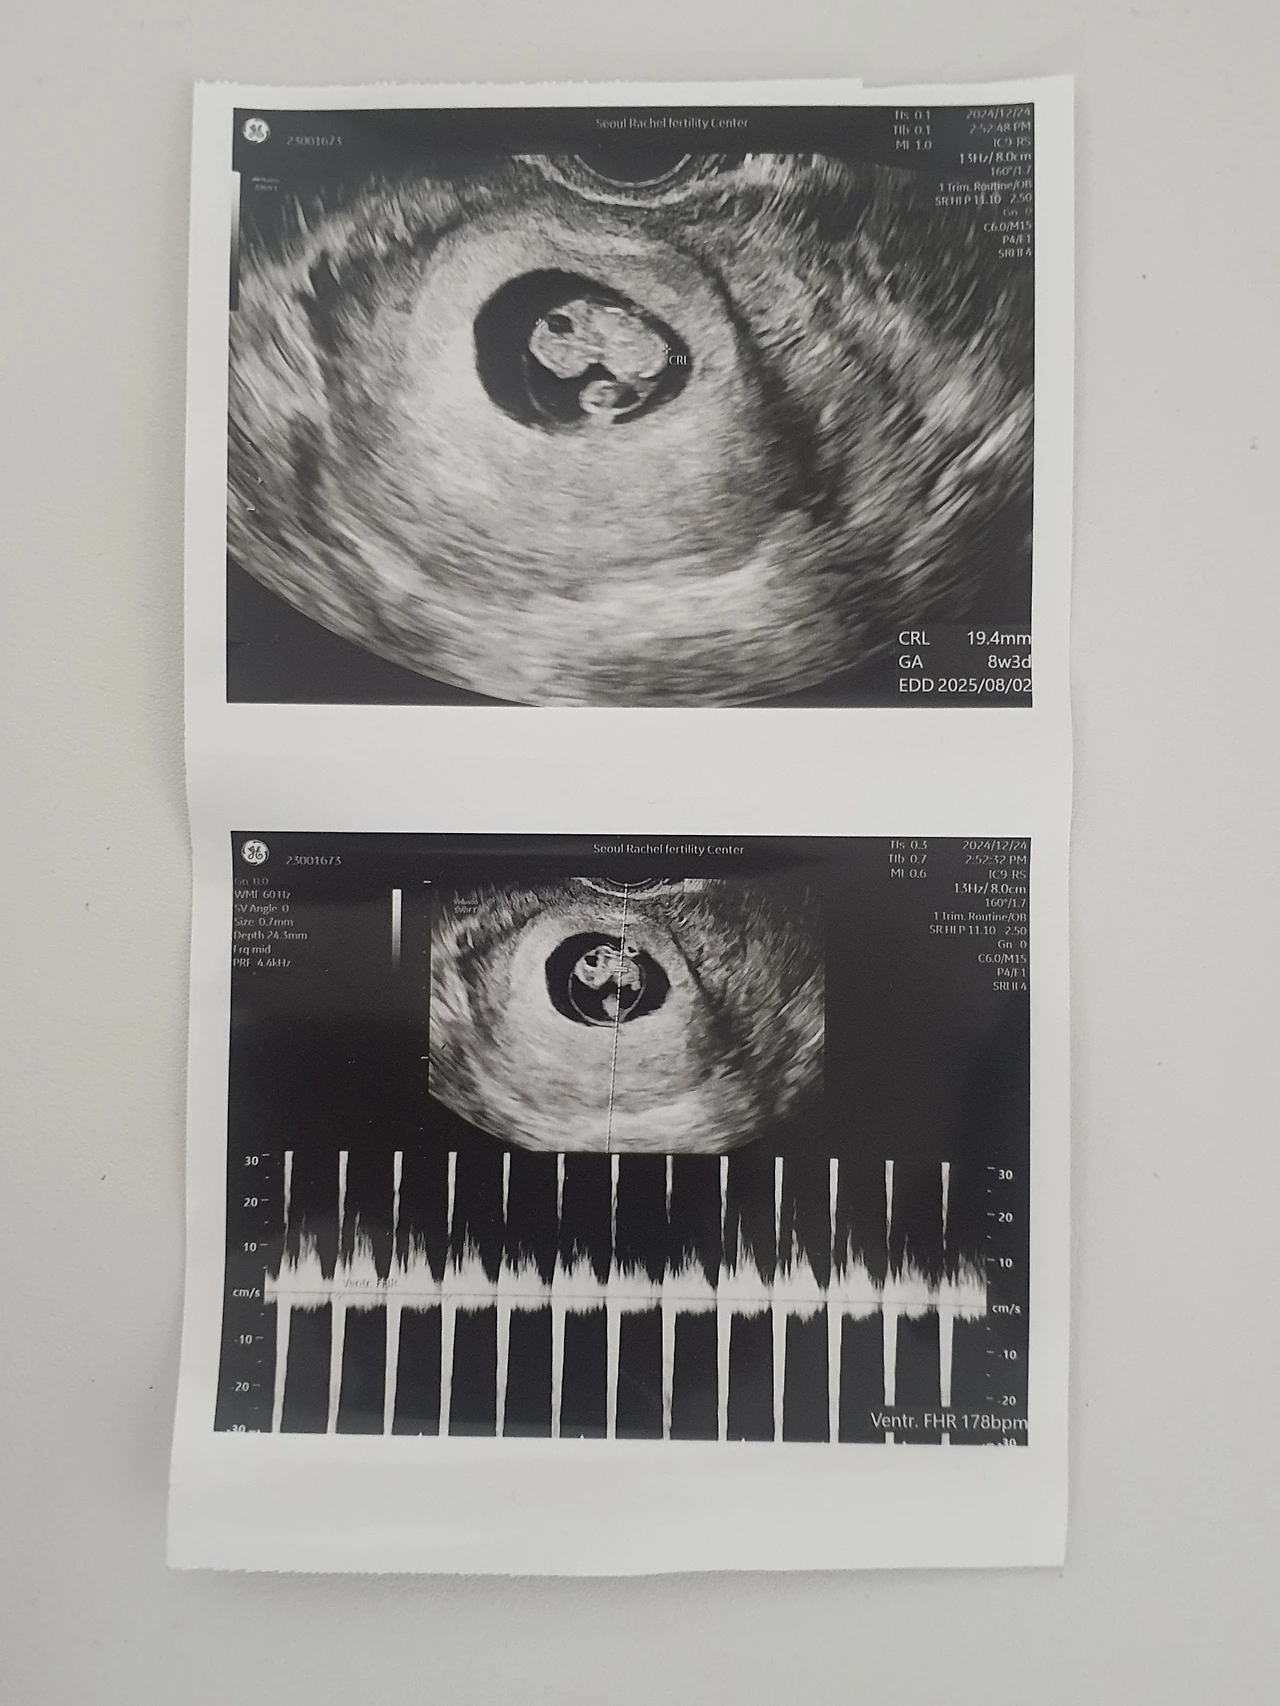

더욱 감사한 것은 우리에게 찾아온 아기의 소식이다. 3번의 달거리를 지나고 그다음 달에 임신을 하게 되었다. 유산을 하고 집에서 쉬는 한 달 간은 누군가 아기들을 빼앗아갔다는 원망과 억울함, 상실감 같은 부정적인 감정들이 옭아 매어 자주 나를 밤마다 울게 했다. 그러던 날들이 지나고 다시 임신을 하게 되니 이 얼마나 놀랍고 감사한 일이었는지 모른다. 사실은 방금 쓴 앞문장 속에서 육 할 정도가 진실이다. 임신을 하니 두려웠다. 다시 잘 못 될까 봐 쉽게 알리지 못했고, 또 반대 감정으로 빨리 여기저기 알리고 싶기도 했다. 이 두 감정이 널뛰는 사이 어느덧 뱃속 아가는 14주가 되었고 조금씩 지인들에게 임신 소식을 알리기 시작했다.

내리 아들을 낳으면 또 아들을 낳을 확률이 높다는 말을 들었다. 그래서 삼 형제가 많다고. 그렇게 듣던 말이 현실이 될 줄이야. 놀랍게도 지난 쌍둥이 형제에 이어 뱃속 아가는 왕자님이었다. 설마 또 아들일까 싶었던 마음에서 성별을 알게 된 나와 남편은 킥킥 웃는 카톡을 나눴다.